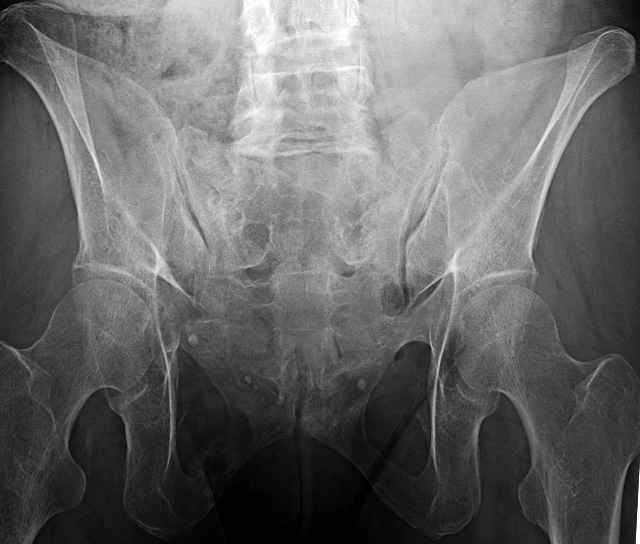

3 Months After Fall

Continued Pain & Immobility

(+) Instability to Compressive Manual Exam

Percutaneous Fixation

(B) Ramus-Retrograde

2 TransIliac-TransSacral

Upper Segment